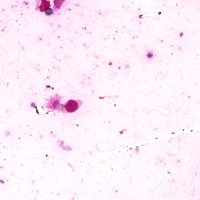

Medical Diagnosis: The "4class" model can be employed by pathologists to accurately identify and quantify the different cell types in blood and tissue samples, assisting in the diagnosis of various blood disorders and diseases, including anemia, leukemia, and infections.

Research and Drug Development: Researchers can use the "4class" model to analyze cellular response to experimental treatments, providing essential data for drug discovery, evaluating the efficacy of novel compounds, and understanding cell behavior under various conditions.

Education and Training: The "4class" computer vision model can serve as an educational tool for medical students and professionals, facilitating their understanding of different cell types, their characteristics, and functions, while promoting accurate identification in laboratory settings.

Automated Screening: Integration of the "4class" computer vision model into medical laboratory equipment can automate the process of cell classification during screenings or biopsies. This can help save time and reduce the risk of human errors during the evaluation of samples.

Telemedicine and Remote Analysis: The "4class" model can support telemedicine platforms, making it possible for healthcare professionals to remotely access and evaluate blood and tissue samples. This would be particularly useful in underserved areas, where access to pathologists might be limited.